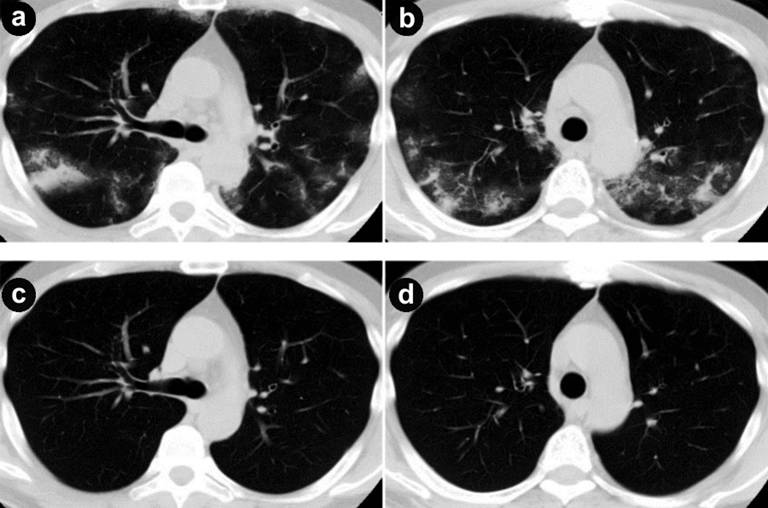

A fifty-five-year-old male had been admitted to our hospital for pancreatic cancer. He was not a smoker and had no history of pulmonary disease. An abdominal computed tomography (CT) scan revealed a tumor measuring 30 mm in diameter at the head of the pancreas (Figure 1a) with multiple liver metastases (Figure 1bc). He was treated with gemcitabine in combination with erlotinib. Gemcitabine was administered with a protocol of 1,000 mg/m2 weekly for 3 weeks followed by 1 week rest. Erlotinib was administered with a protocol of 100 mg/body every day. One week after starting erlotinib, he developed a skin rash - mainly affecting the face and neck - which was controlled by oral minocycline without worsening. On the 13th day of erlotinib treatment, he presented with a fever elevated up to 40 degrees. No clinical focus of infection was found. Vital signs were stable, white blood cell (WBC) count was within normal limits (6,400 µL-1; reference range: 0-9,000 µL-1), and C-reactive protein (CRP) was slightly elevated (1.98 mg/dL; reference range: 0-0.1 mg/dL). On the next day, the high fever continued and WBC count elevated to 11,800 µL-1. CRP level was also elevated to 16.09 mg/dL. The percentage of blood eosinophil was within normal limits (1%; reference range: 2–6%). Serum KL-6 level was within normal limits (448 U/mL; reference range: 0-499 U/ml). Chest X-ray revealed reticular shadow in the bilateral lung fields. Chest CT scan showed a diffuse ground-glass like infiltration of both lungs without any sign of pulmonary edema or pleural effusions (Figure 2ab). He was diagnosed with ILD, and a high-dose corticosteroid with an antibiotic agent therapy was introduced. Prednisolone was applied with an initial dose of 1,000 mg/day for 3 days and an antibiotic agent was also applied for 3 days. After that, the reticular shadow was reduced gradually on CT. Following a high-dose corticosteroid pulse therapy, prednisolone was applied for internal use with a dose of 60mg/day. Two weeks after the introduction of steroid therapy, the ILD faded away on CT (Figure 2cd). The dose of corticosteroid was gradually decreased by half every 2 weeks. Corticosteroid therapy was continued for 10 weeks. For detection of allergic response against erlotinib and gemcitabine, drug-induced lymphocyte stimulation test (DLST) was performed 4 weeks after occurrence of ILD. The stimulation indices were 84% of the control in gemcitabine and 88% in erlotinib, and therefore judged as negative.

Figure 2. a., b. Chest computed tomography (CT) shows the onset of interstitial lung disease (ILD) on both lung fields. c., d. ILD are faded out on chest CT two weeks after the introduction of steroid therapy. |